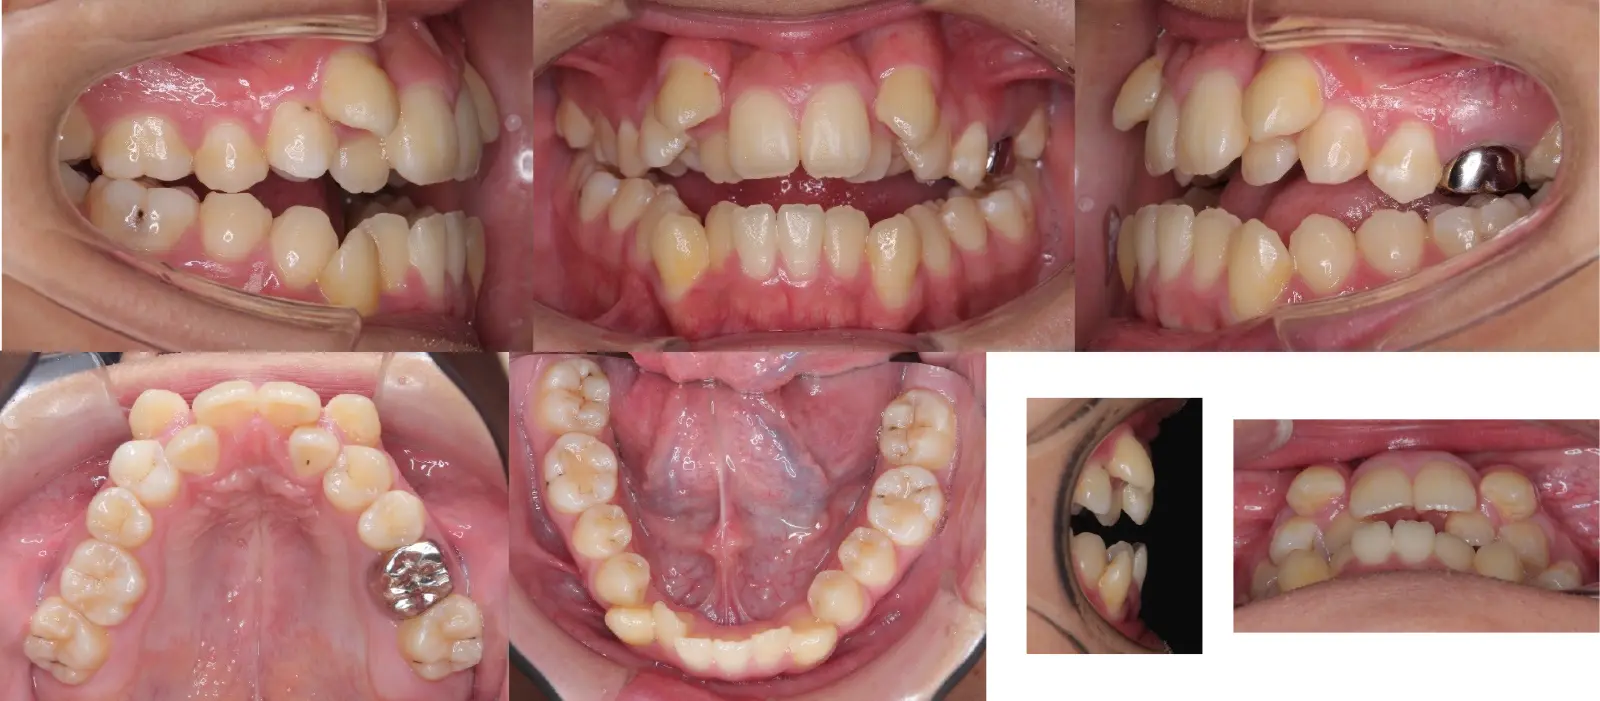

Angle Ⅱ級、叢生を伴う開咬

- 主訴

歯のガタガタ、前歯で噛めない

- 年齢

初診時10代

- 治療期間

36か月

- 治療回数

30回

- 治療に用いた主な装置

ハーフリンガル装置(Incognito&Alexander装置)、口蓋型歯科矯正用アンカースクリュー(i-station)

- 治療費

1,250,000円(税別)トータル料金

- 抜歯部位

上下顎第1小臼歯